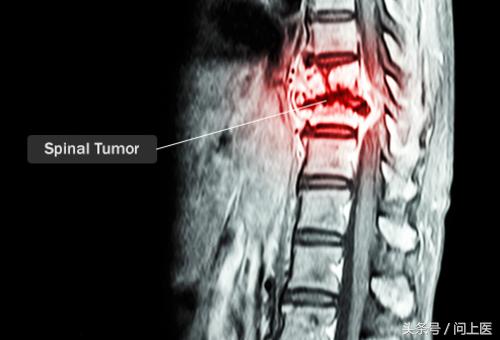

9. 脊髓肿瘤

脊髓肿瘤生长在脊髓附近,它会压迫和损伤神经,影响脊柱和脊椎。脊髓肿瘤有良性和恶性之分,但是与其他部位的肿瘤不同,良性的脊髓肿瘤也会造成严重的后果甚至危及生命。脊髓肿瘤可能最先导致颈部疼痛,还可能导致背部疼痛、腿脚无力、麻木。

脊髓肿瘤如何治疗?

脊髓肿瘤的治疗取决于肿瘤的类型和部位。可能需要手术切除压迫神经的肿瘤,还可能需要进行放疗和化疗以消除癌细胞。